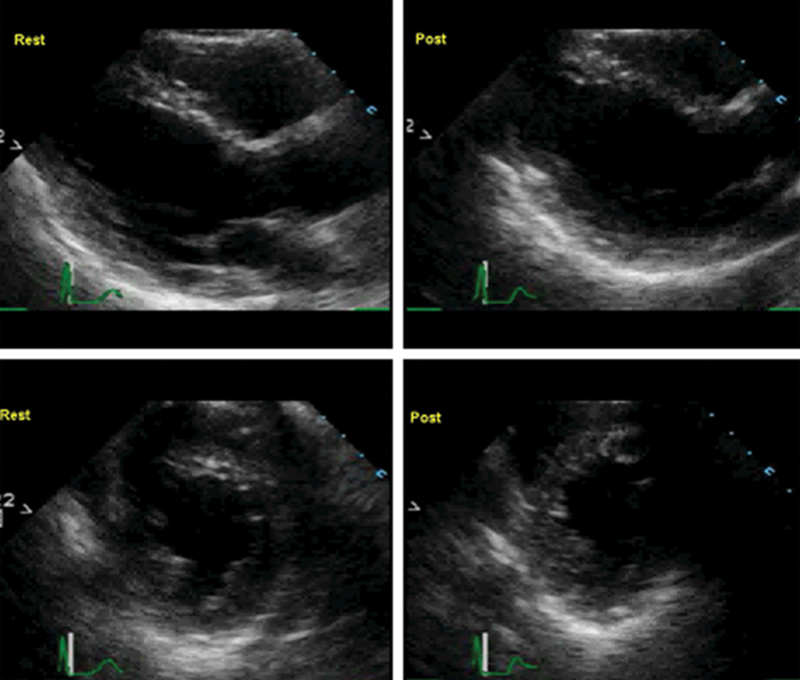

فحوصات تشخيصية لبعض امراض القلب والشرايين التاجية